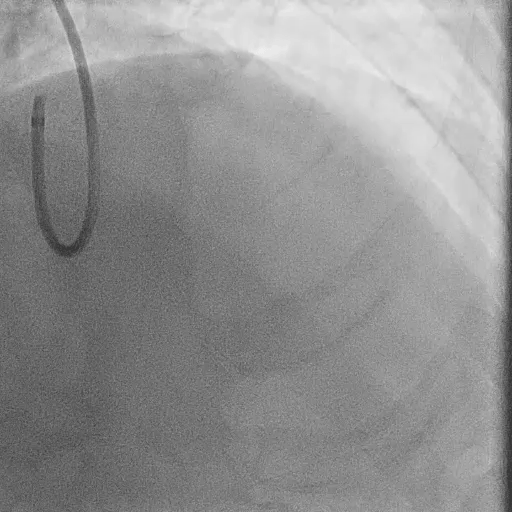

During LM-LAD PCI

Predilation with 4.0/15 mm NC Scoreflex balloon

Implantation of 4.0/34 mm DES from LM to LAD

POT with 5.0/15 mm NC balloon